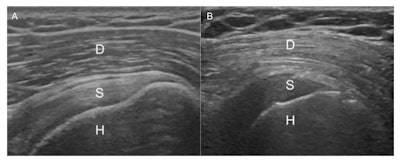

Musculoskeletal ultrasound is often used to diagnose shoulder pain, and over the course of his practice, Soliman has noticed a pattern in which patients who have a bright deltoid muscle on ultrasound are also diabetic or prediabetic. He and colleagues conducted a study to determine if this brightness could predict the disease.

The study included 124 shoulder ultrasound scans from patients with type 2 diabetes and 13 from people with prediabetes; diabetes was confirmed via hemoglobin A1c level measurements. The study also included 49 ultrasound scans from nondiabetic obese patients, with obesity determined by body mass index. Two musculoskeletal radiologists blinded to the diabetic status of the patients reviewed the images and categorized them as normal, suspected diabetic, or diabetic; a third reader arbitrated cases in which the other two radiologists disagreed.

Of the 137 diabetic ultrasound scans included in the study, 31 (22.6%) were categorized as normal, 36 (26.2%) as suspected diabetic, and 70 (51.2%) as definitely diabetic. Brightness in the deltoid muscle on ultrasound had a positive predictive value for diabetes of 89%. It was also an effective predictor of prediabetes: Of the 13 prediabetic ultrasound scans reviewed, the readers categorized all as either "suspected diabetic" or "definite diabetic."

Why the deltoid muscle is bright on ultrasound in diabetic or prediabetic patients isn't completely understood, but the researchers theorized that it's because of low levels of glycogen in the muscle, which can be depleted in people with the disease.